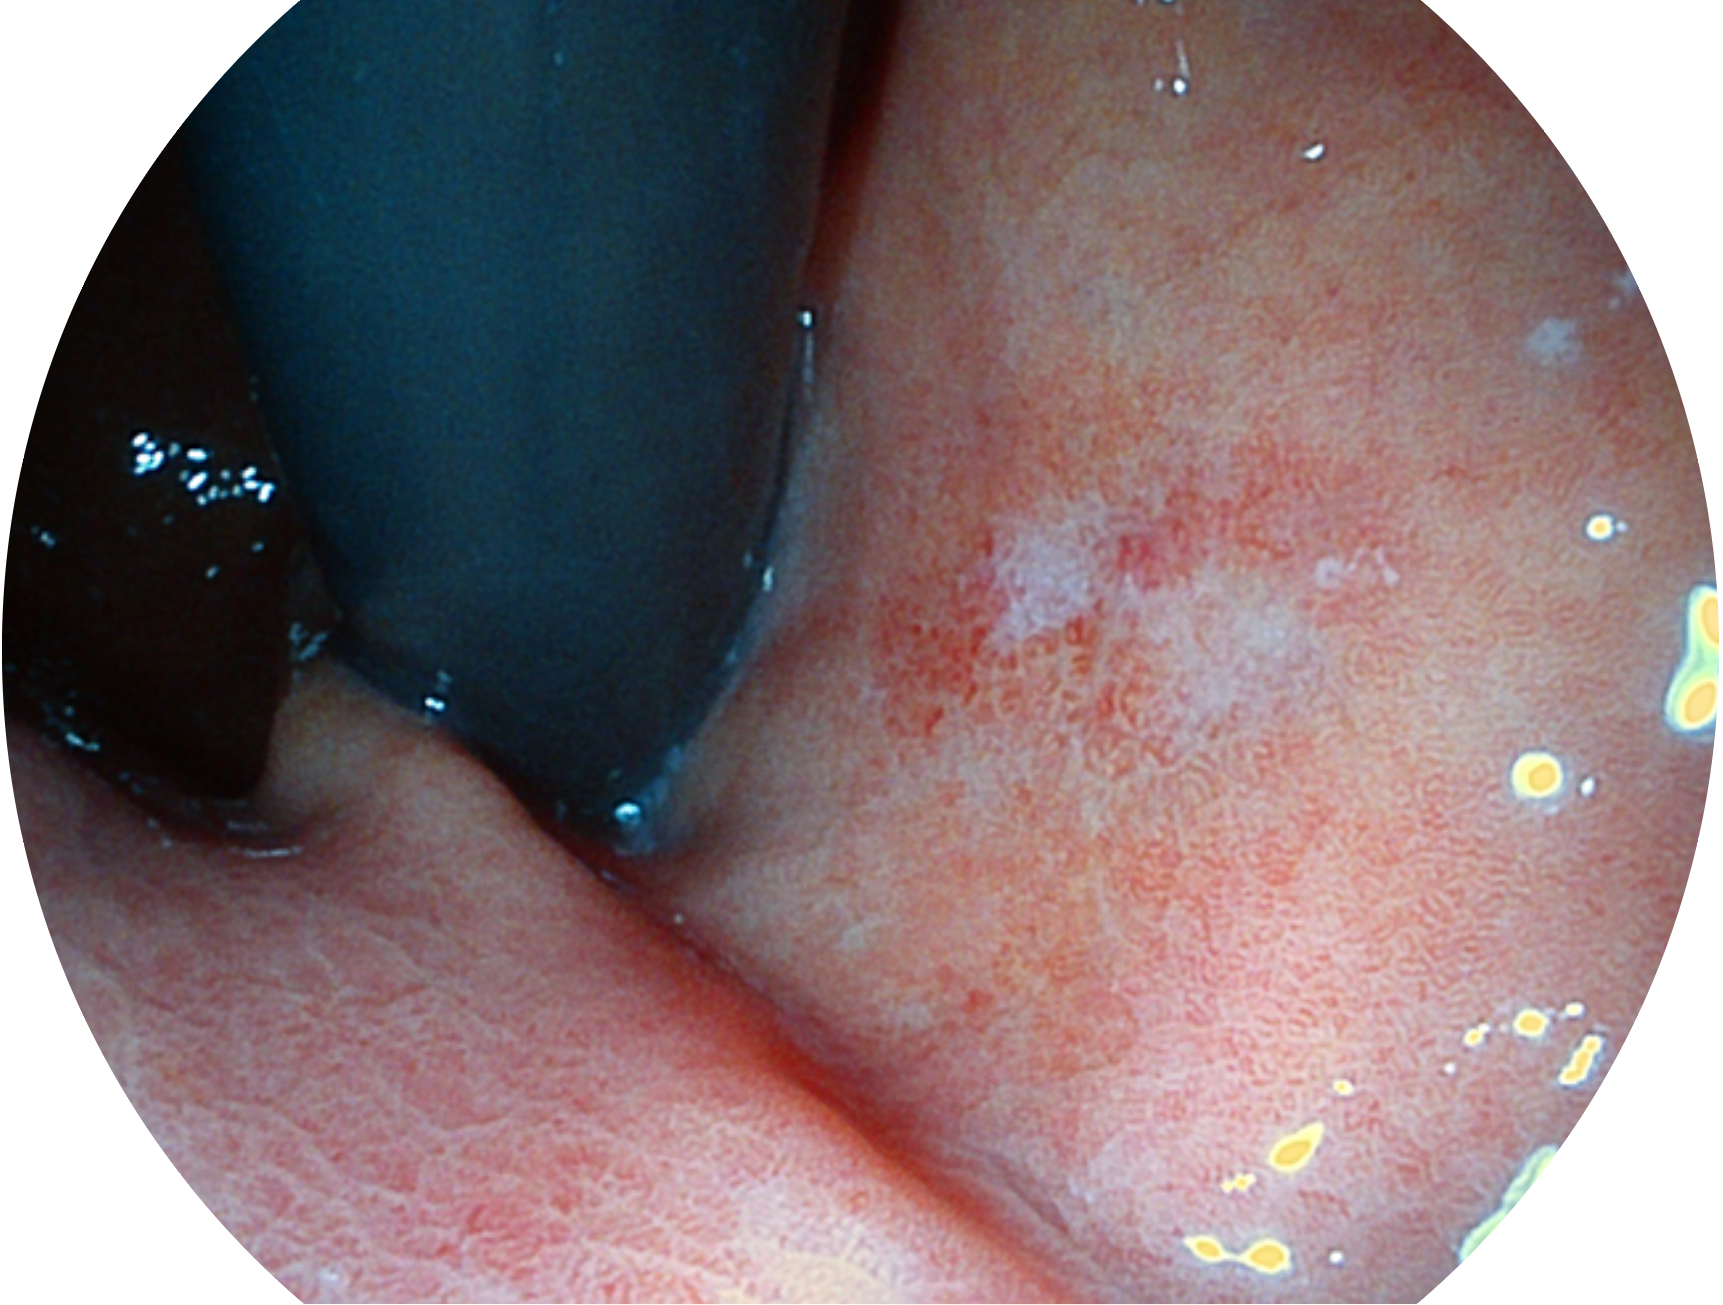

DB中国旗舰官方网站新开发的内镜染色技术,主要是基于多波长LED 光源的开发,VLS-55Q 四波长LED 光源是由四个不同颜色的LED光按照相应照明模式所规定的特定发光比例进行合束后形成,合束后形成的照明光的光谱由红光、绿光、蓝光及蓝紫光这四个不同的波段范围构成。具有更高光谱自由度,通过光谱比例的控制,实现了聚谱成像技术,英文全称为“Spectral Focused Imaging, SFI”,缩写为“SFI”和光电复合染色成像技术,英文全称为“Versatile Intelligent Staining Technology, VIST”,缩写为“VIST”。